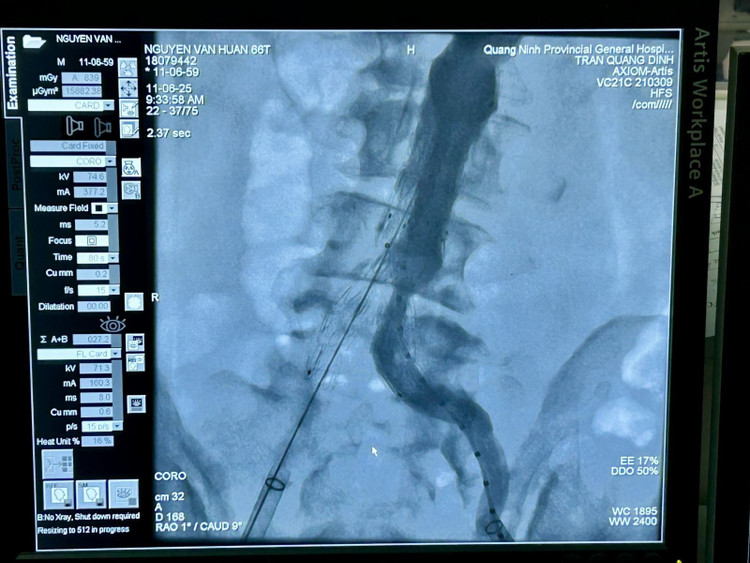

Ca can thiệp do BSCKII Trần Quang Định, Trưởng khoa Phẫu thuật và Can thiệp Tim mạch thực hiện với sự hỗ trợ của chuyên gia. Ê-kíp tiến hành đặt stent graft tại vị trí khối phình động mạch chủ bụng đoạn dưới thận và 2 stent nhánh vào động mạch chậu hai bên.

Stent graft được đưa vào đoạn mạch bị phình rộng tạo thành một giá đỡ vững chắc, có tác dụng như một màng bọc bảo vệ thành động mạch chủ bị tổn thương, ngăn nguy cơ vỡ khối phình. Quá trình can thiệp kéo dài gần một giờ, bệnh nhân tỉnh táo và không có cảm giác đau.

stnet-1.jpg

Hình ảnh chụp từ hệ thống DSA cho thấy stent graft đã được đặt đúng vị trí khối phình động mạch - Ảnh BVCC